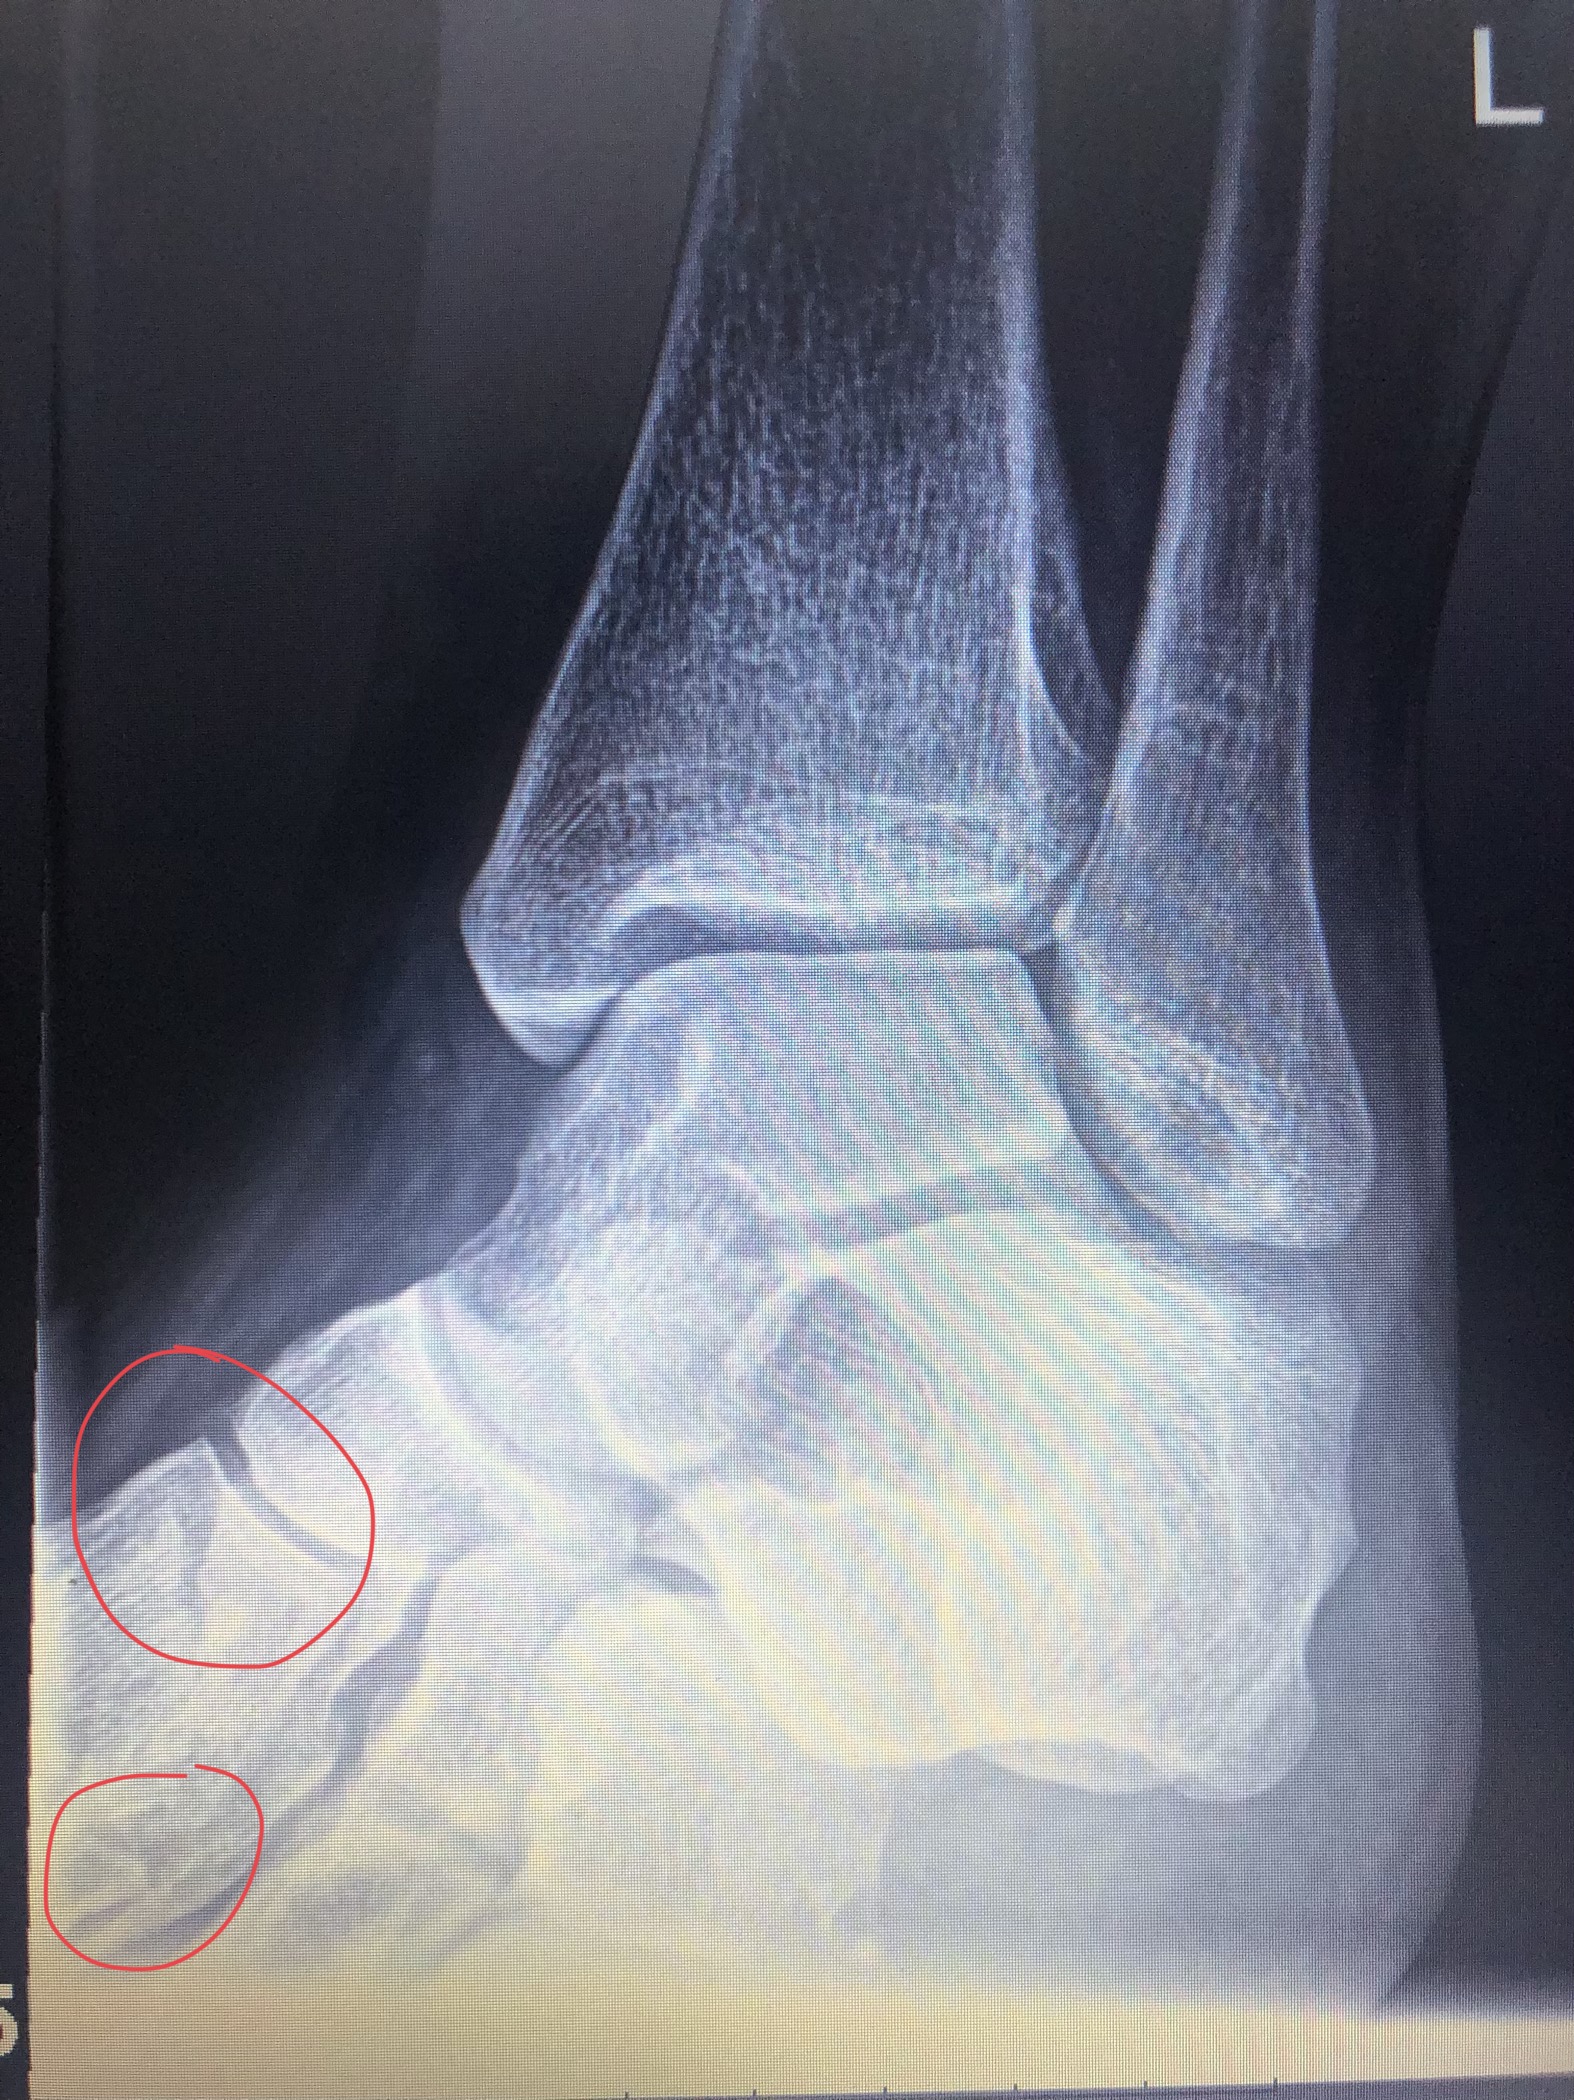

Fraktur oder Bänderriss? (Schmerzen, Sprunggelenk)

Fraktur oder Bänderriss am SprunggelenkWenn Sie Schmerzen im Sprunggelenk verspüren, kann es sein, dass Sie eine Fraktur oder einen Bänderriss haben. Es ist schwer zu sagen, welche von beiden Verletzungen vorliegt, ohne eine Röntgenaufnahme oder eine MRT. Ebenso kann es schwer sein, festzustellen, ob eine Fraktur oder ein Bänderriss ohne eine genauere Diagnose vorliegt. Ein Arzt kann Ihnen bei der Erstellung einer Diagnose helfen und Ihnen helfen, die richtige Behandlung zu erhalten, um Ihre Verletzung richtig zu behandeln und in Zukunft ein Problem zu vermeiden.

Bei Verletzungen kann es schwierig sein, eine sichere Einschätzung vorzunehmen, aber es ist wichtig, dass Sie sich mit Ihrem Arzt absprechen, um eine fundierte Entscheidung zu treffen. Zu befolgende Anweisungen, Ruhe und eine gute Behandlung sind entscheidend, damit Verletzungen richtig heilen können und Sie sich zu 100% wieder gesund fühlen und wieder aktiv in Ihrem Alltag werden können.